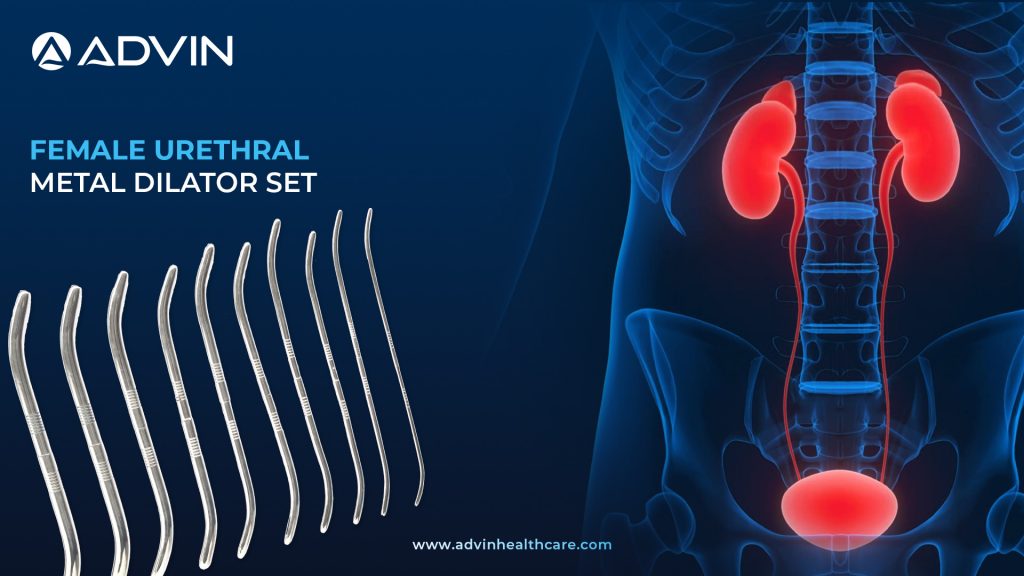

Female Urethral Metal Dilator Set – Safe & Effective Dilation

Introduction to Female Urethral Metal Dilator Set: Precision Tools for Urethral Dilation The Female Urethral Metal Dilator Set is used to treat urethral strictures and maintain urethral patency in women. It consists of a series of stainless steel dilators in gradually increasing sizes. This set allows for gentle and controlled...